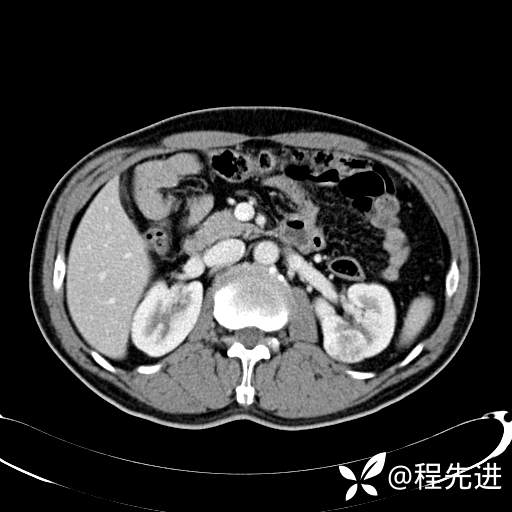

患者性别:男

患者年龄:65岁

简要病史:腰痛2月,体检发现左肾占位5天

平扫: